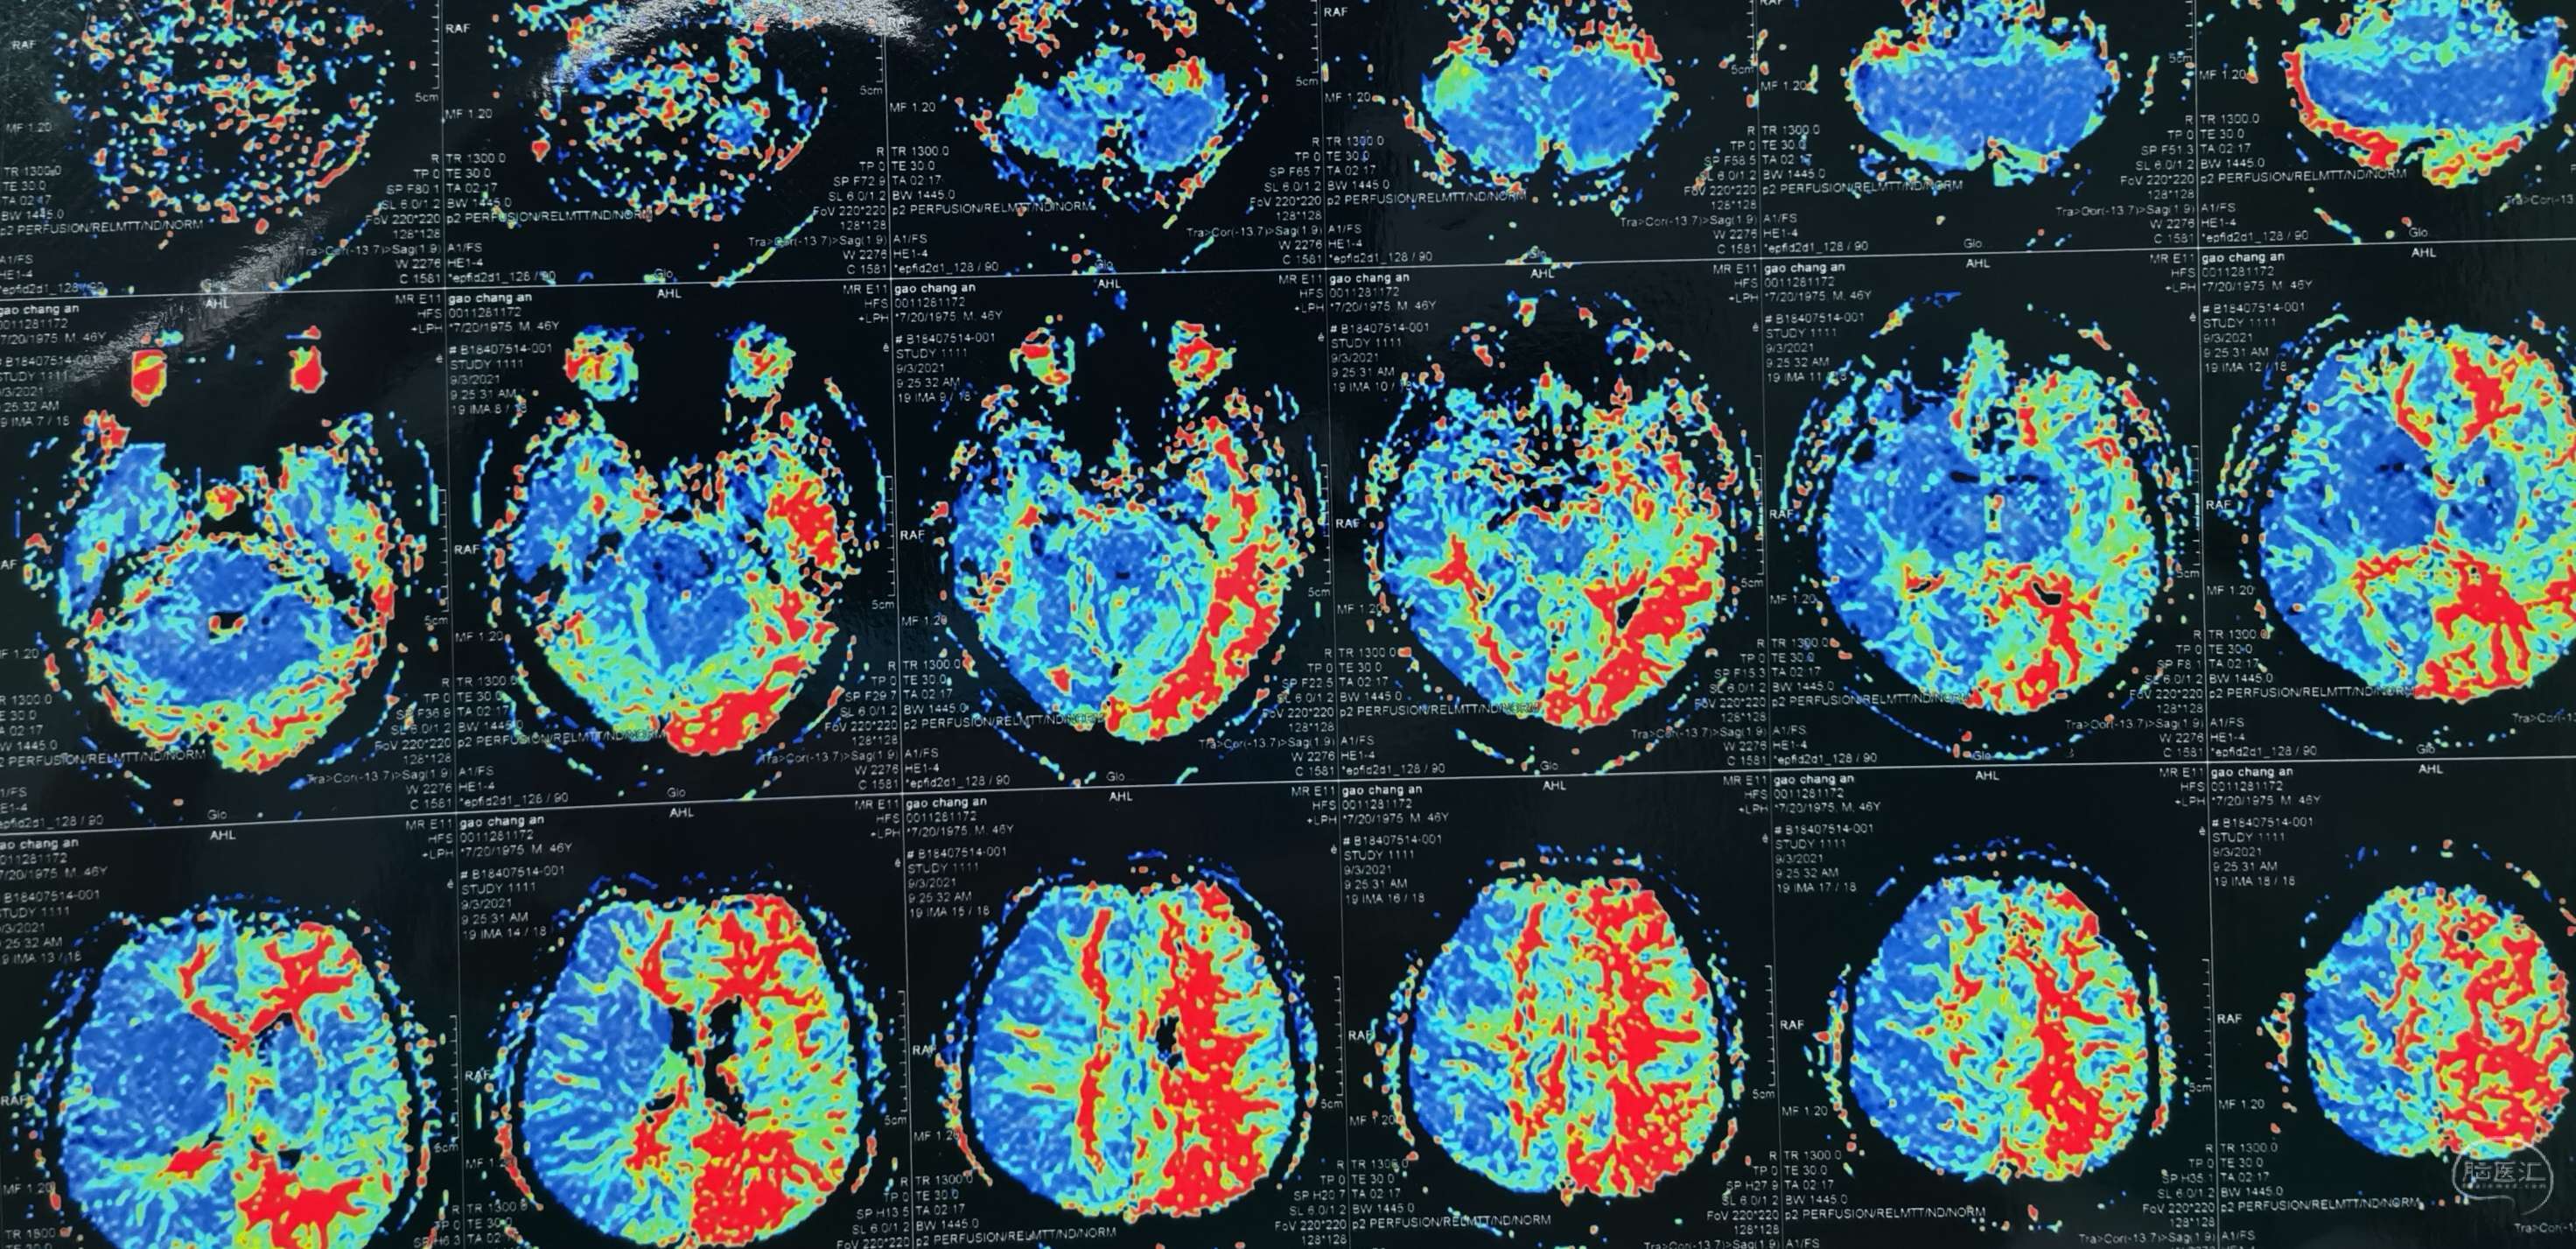

磁共振灌注提示:左侧大脑半球低灌注改变。

磁共振灌注提示:双侧大脑半球低灌注改变。